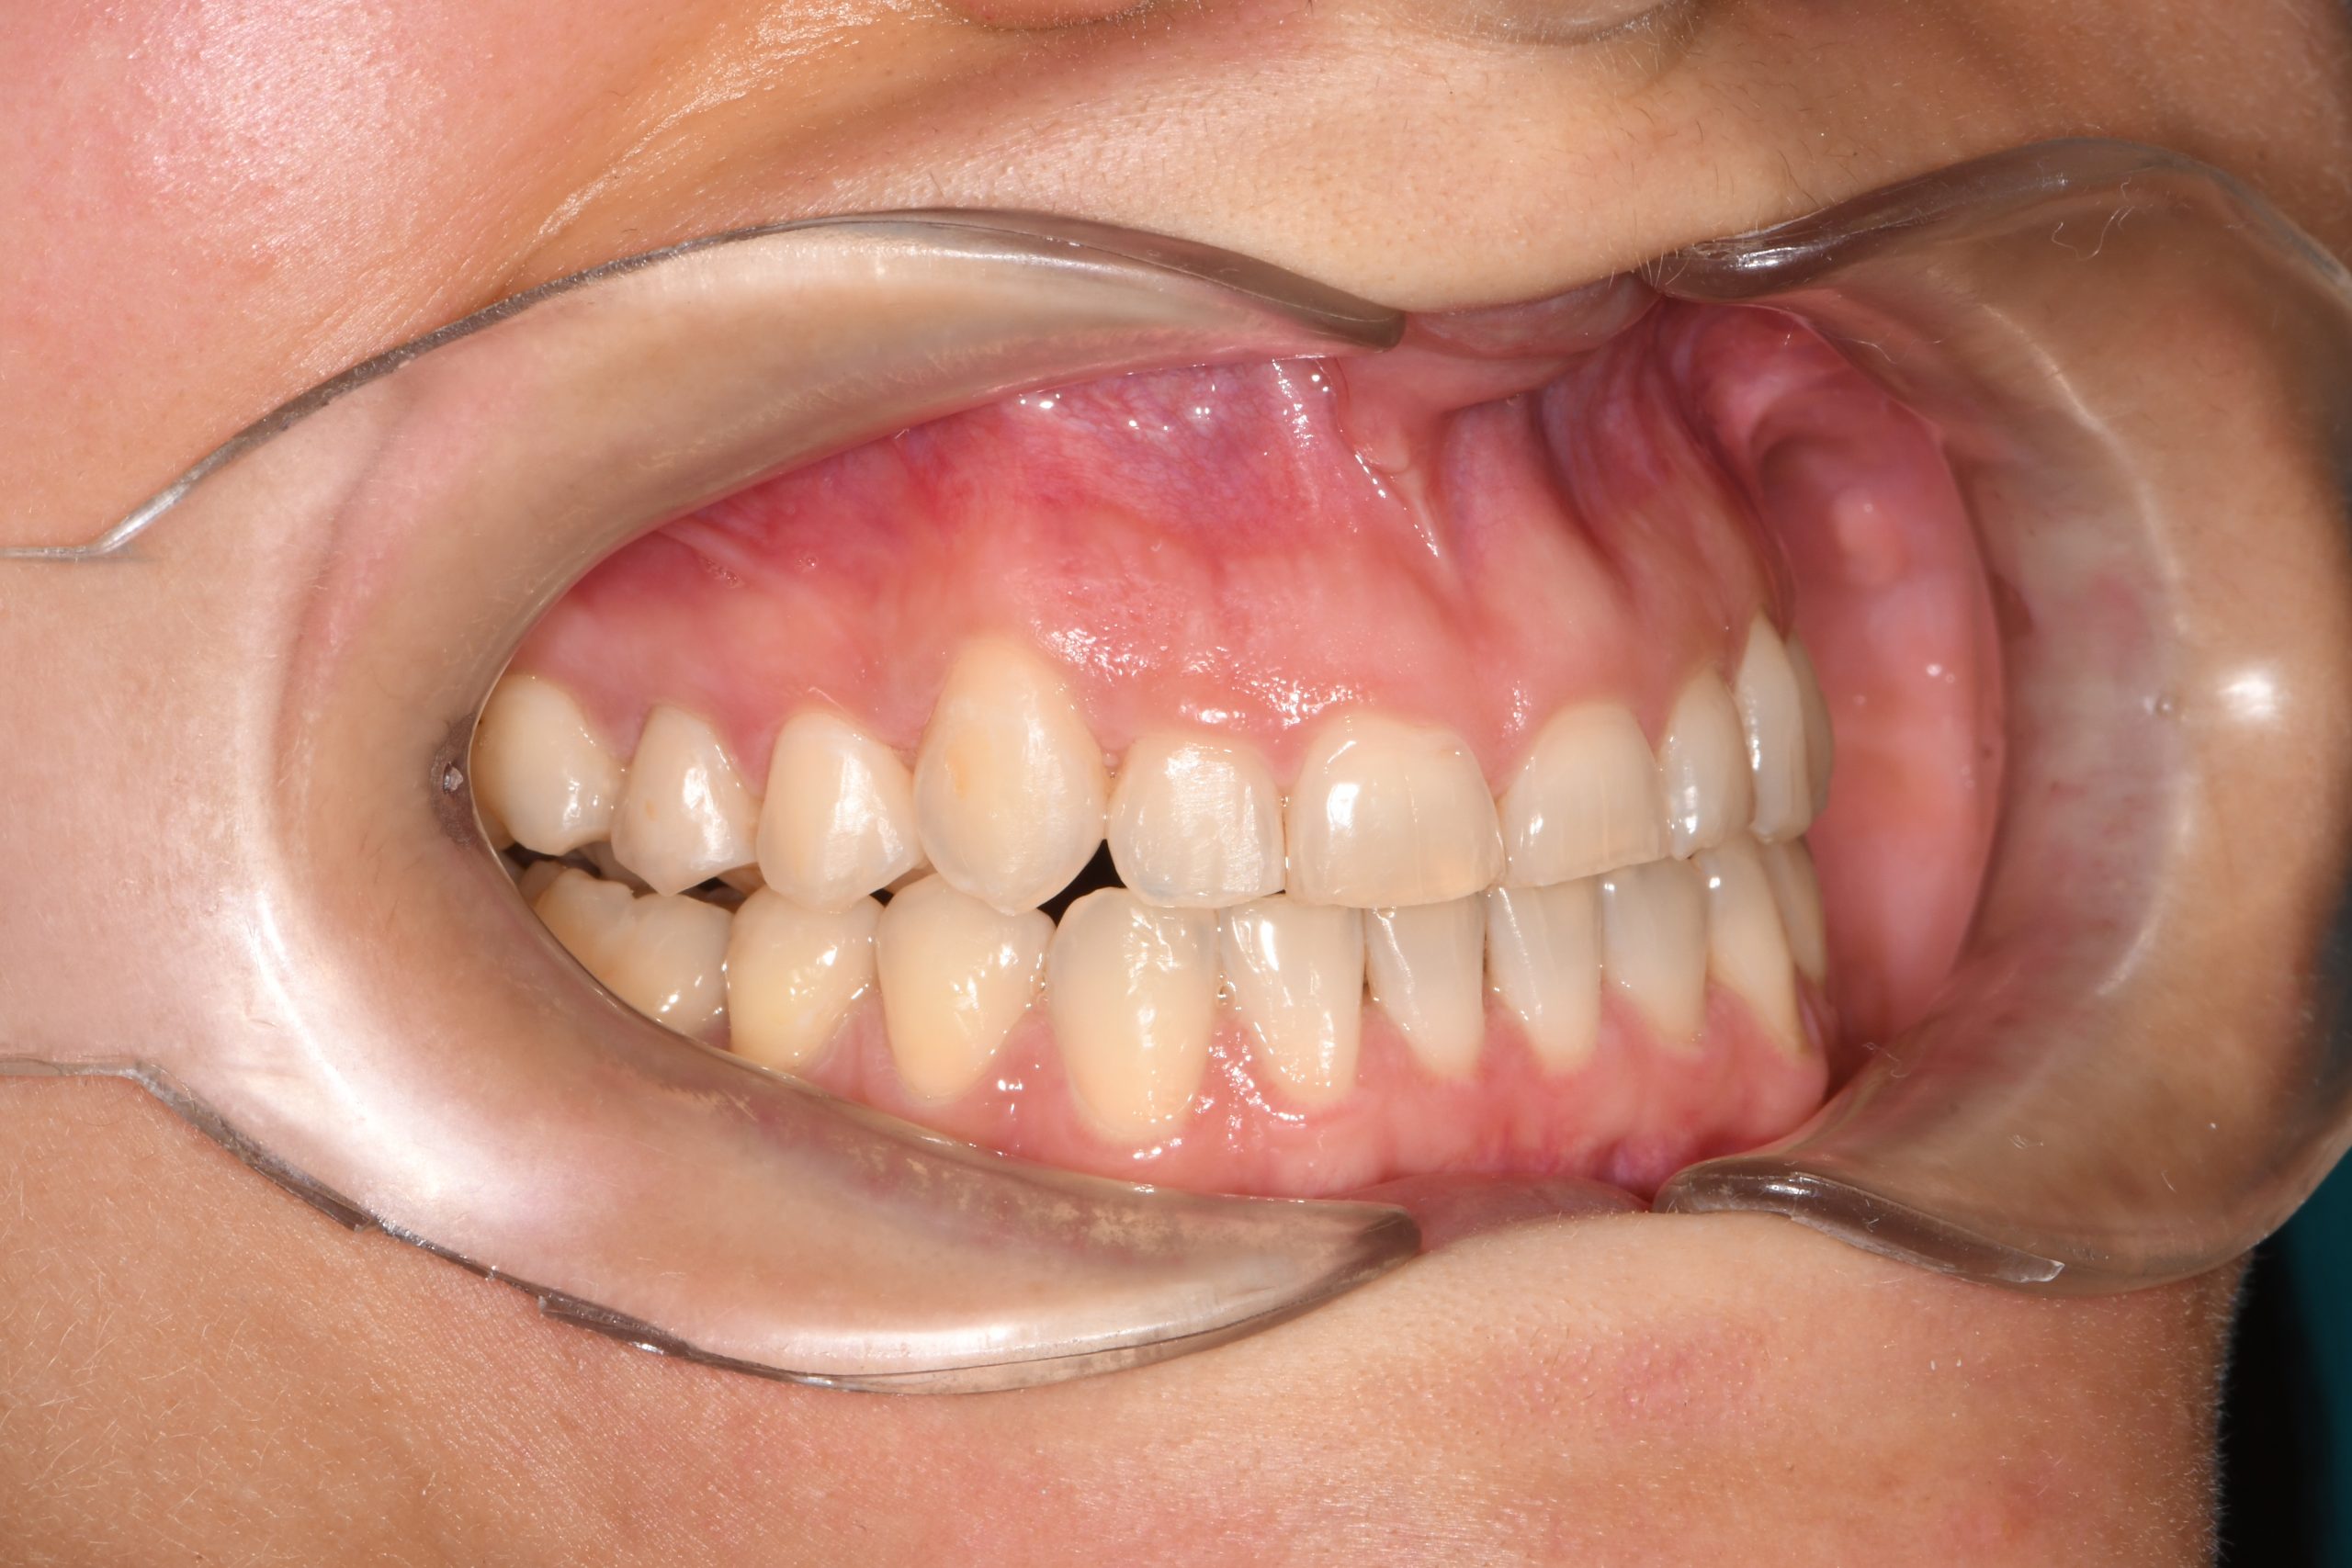

Az elmúlt évekből rengeteg szakmai referenciát tudnánk bemutatni, amelyek különböző fogszabályozási problémákat oldottak meg. Válogatva a több száz esetből, ezen az oldalon olyan képeket, információkat igyekeztünk bemutatni, amelyeknek a segítségével a jövőbeni pácienseinknek azt tudjuk üzenni: A Te fogsorod is lehet gyönyörű!

(Képeket a Pácienseink külön írásos beleegyezésével mutatjuk be!)